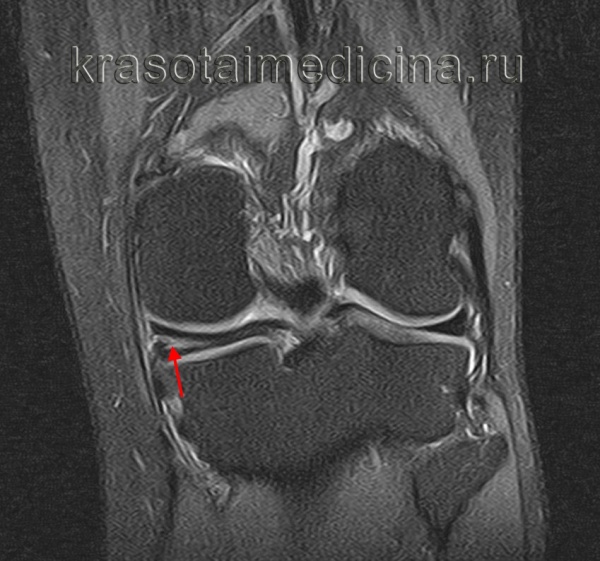

УЗИ не позволяет произвести четкую визуализацию изменений суставного хряща и внутрисуставных структур. [15] С помощью МРТ можно с 85% точностью выявить изменения костных, хрящевых и мягкотканых структур сустава, а также субхондральной кости. [15] С помощью сцинтиграфии можно оценить метаболическую активность периартикулярной костной ткани.

(Слева) МРТ Т2ВИ, режим подавления сигнала от жира, коронарный срез: у пациента 13 лет с болью в колене определяется неполный дискоидный латеральный мениск, который сужается к центру, но покрывает большую часть латеральной поверхности большеберцовой кости. Нормальный латеральный мениск должен покрывать около 50% поверхности большеберцовой кости.

(Справа) MPT PDВИ, коронарный срез: определяется частичный дискоидный медиальный мениск с горизонтальным разрывом. Дискоидные мениски имеют тенденцию к разрыву в большей степени, чем нормальные вследствие увеличения осевой нагрузки и трещины в неабсорбированных областях в центре фиброзного хряща. (Слева) МРТ PDВИ, последующие сагиттальные изображения: определяются признаки дискоидного латерального мениска. При использовании сагиттальных изображений толщиной 3-4 мм обычно не должно визуализироваться более трех полных срезов мениска до отделения переднего и заднего рога; у этого пациента таких срезов пять (самое медиальное изображение отсутствует).

(Справа) МРТ Т2ВИ, режим подавления сигнал от жира, коронарный срез: определяется дискоидный латеральный мениск, содержащий обширный патологический горизонтальный сигнал, указывающий на горизонтальный разрыв. (Слева) МРТ Т2ВИ, режим подавления сигнала от жира, коронарный срез: у пациента 10 лет определяется смещение разорванного дискоидного латерального мениска. Место прикрепления к капсуле разорвано, а более медиальная часть смещена кпереди от межмыщелковой вырезки.

(Справа) МРТ PDВИ, режим подавления сигнала от жира, сагиттальный срез: у этого же пациента определяется крупный латеральный фрагмент мениска в межмыщелковой вырезке с широким пучком повышенного сигнала внутри, характерным для горизонтального разрыва.

2. МРТ при дискоидном мениске коленного сустава:

• Коронарные изображения: утрата нормального сужения, клиновидная форма центрального мениска:

о Частичный дискоидный мениск суживается, но в медиально-латеральном направлении он шире, чем нормальный (>14 мм)

• Сагиттальные изображения: признак продолжающегося вещества мениска в передне-заднем направлении (зависит от толщины среза)

- МРТ коленного сустава. Является золотым стандартом при данной патологии. Подтверждает повышенную толщину мениска, нарушение соотношений между максимальным диаметром и шириной рогов, изменение соотношений между шириной мениска и тибиального плато.